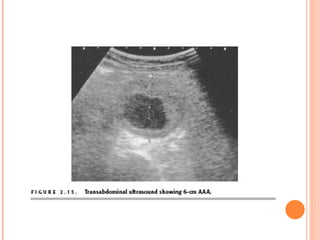

Cross-sectional ultrasound of a 6-cm abdominal aortic aneurysm. Note mural thrombus and eccentrically shaped patent lumen .

Cross-sectional ultrasound ofa 6-cm abdominal aortic aneurysm. Note mural thrombus and eccentrically shaped patent lumen .